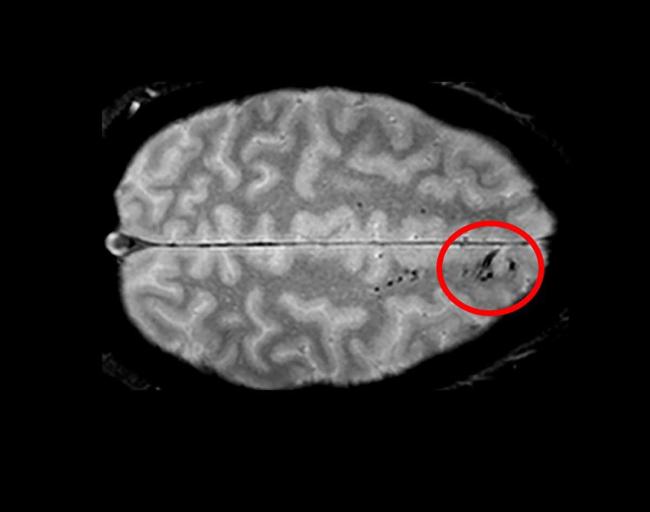

Using advanced imaging, researchers have uncovered new information regarding traumatic microbleeds, which appear as small, dark lesions on MRI scans after head injury but are typically too small to be detected on CT scans. The findings published in Brain suggest that traumatic microbleeds are a form of injury to brain blood vessels and may predict worse outcomes. The study was conducted in part by scientists at the National Institute of Neurological Disorders and Stroke (NINDS), part of the National Institutes of Health.

The results showed that 31% of all study participants had evidence of microbleeds on their brain scans. More than half (58%) of participants with severe head injury showed microbleeds as did 27% of mild cases. The microbleeds appeared as either linear streaks or dotted, also referred to as punctate, lesions. The majority of patients who exhibited microbleeds had both types. The findings also revealed that the frontal lobes were the brain region most likely to show microbleeds.

The family of a participant who died following completion of the study donated the brain for further analysis. Dr. Latour’s team imaged the brain with a more powerful MRI scanner and conducted detailed histological analysis, allowing the pathology underlying the traumatic microbleeds to be better described. The results showed iron, indicating blood, in macrophages (the brain’s immune cells) tracking along the vessels seen on the initial MRI as well as in extended areas beyond that seen on MRI.